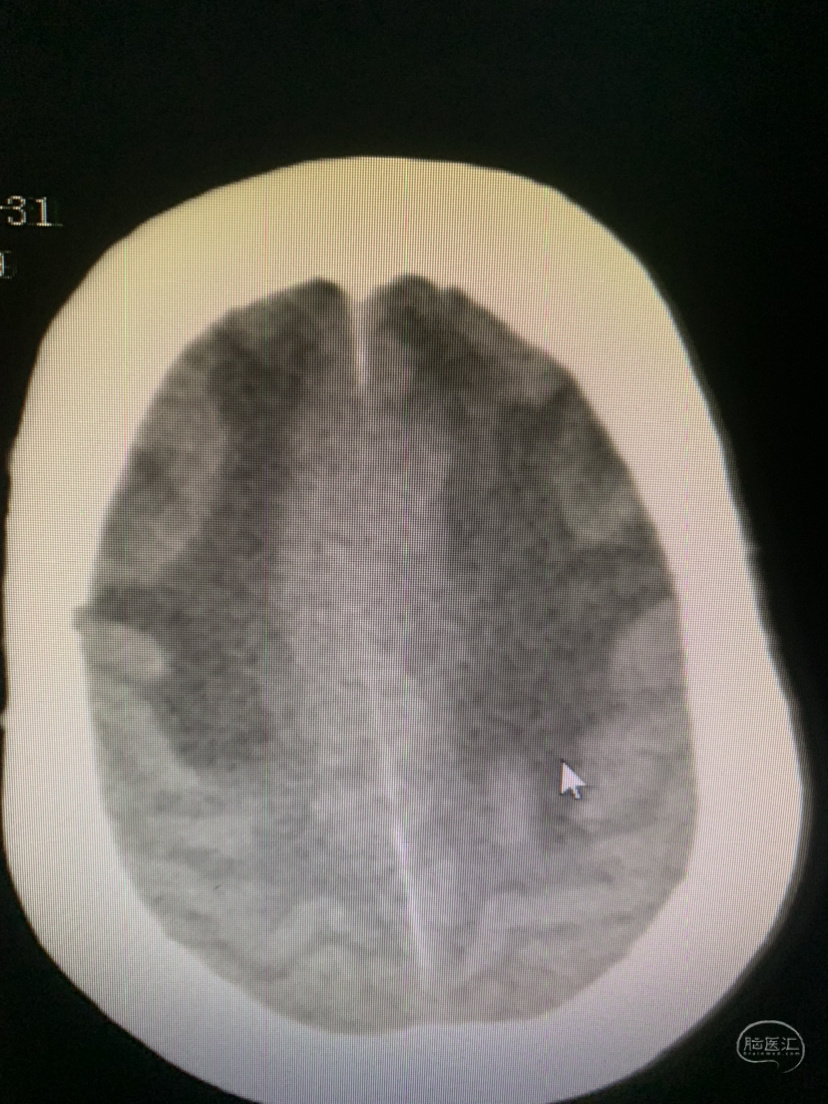

术前术后对比

术后CT